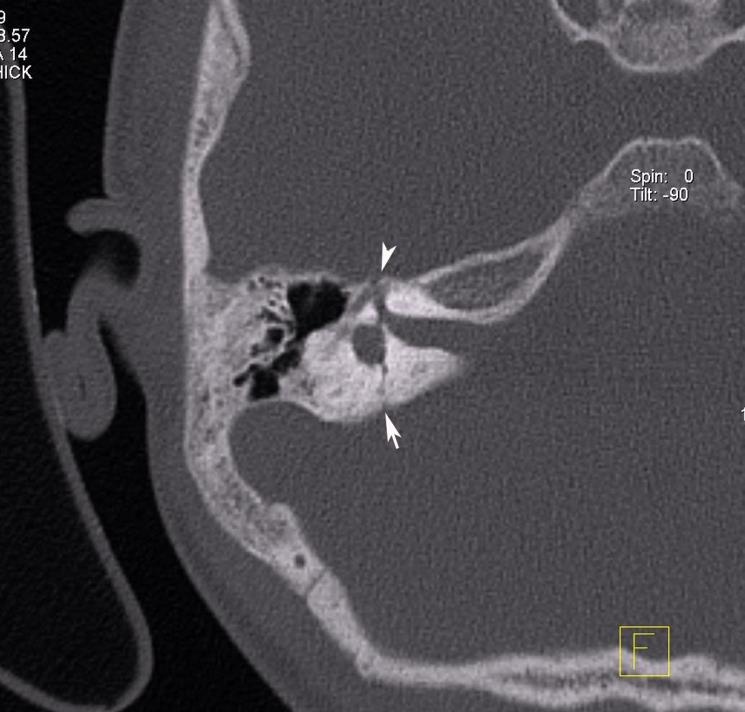

Congenital Cholesteatoma

- Question: 7 years old with hearing loss. No history or ear discharge or infection.

- Answer:

- A- What is the diagnosis?

- Congenital cholesteatoma

- B- What is the treatment?

- Reconstructive surgery and mastoidectomy

Fungal Sinusitis

- Question:

- Fungal sinusitis

- B- What is the surgical treatment?

- Endoscopic sinus surgery